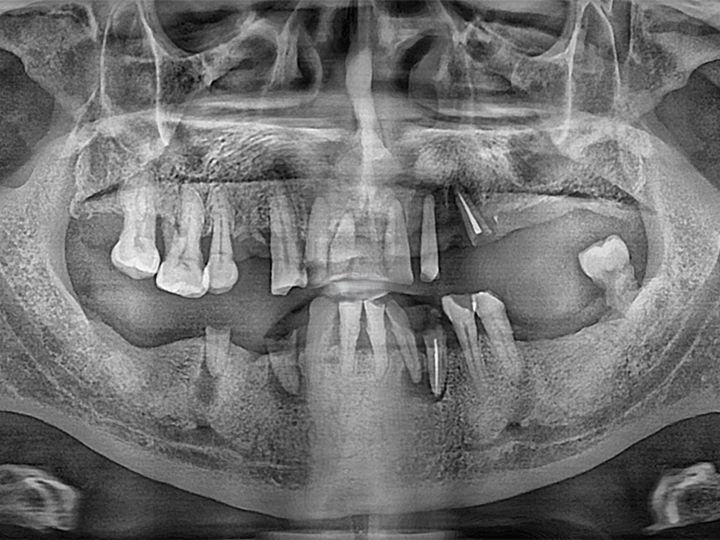

ハル歯科医院は、最先端のインプラント歯科治療に特化したクリニックです。代表のジョー・ハング院長は日本の神奈川歯科大学を卒業し、両国での歯科医師免許を保持。さらに、韓国で専門医資格を取得し、口腔外科など高度な手術経験も豊富です。すべての治療を院長自らが行う専任診療制を採用しており、流暢な日本語で対応可能。「デジタルインプラント」や「無削除ラミネート」などの最新のデジタル歯科治療を、日本の約半額で受けられます。仁川・金浦空港から乗り換えなしで行ける孔徳(コンドッ)駅すぐとアクセスも良好で、旅行者にも便利な立地となっています。

インプラント

匿名さん

日本でインプラント施術を行う予定でいましたが、色々と調べた結果、価格面でこちらで行うことを決めました。

先生との会話も日本語で行えて、海外で施術を受けるという当初の不安は無くなりました。

施術の内容や予算も相談して決められたので安心できました。また継続して訪問させていただこうと思います。

日本のインプラントは高額なのでネットで韓国の歯科医院を探してました 日本語対応の歯科医はいくつかありましたが せつ術医師に直接日本語で話せるということでハル歯科医院を選びました 先生はとても親切で最初の説明からわかりやすく こちらの質問にも全て親切に答えていただきました 5本のインプラントをいちどに入れていただいたのですが とてもスムーズに5本入れることができました 費用もkonest やホームページに書いてあるとおりで 1本140万wから120万wにディスカウントしてもらい レートも一円 10w で計算していただきました 3ヶ月後にまた来院します この歯科医院を選んで良かったと思ってます

海外での初めてのインプラント治療、不安で何回もどうしようか考えた結果こちらの歯科でやって頂く事を決めました。LINEで何度も連絡を取らせて頂き

分からない事、不安な事、細かい事まで色々質問させて頂き2泊3日と言う短期間の旅行の中で

インプラントの埋め込みまで済ませて頂きました。先生が日本語で丁寧に説明してくれ安心して治療を受ける事ができました。

どこまでインプラントを埋め込んだら良いか先生からの提案、説明をお聞きした上でわたし自身の予算などある為自分の希望を話させて頂き

今できる中で希望通りの治療をして頂きました。